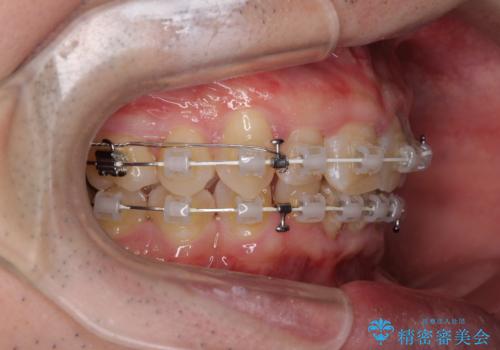

- 矯正装置

- 審美装置

- 治療期間

- 2年4ヶ月

上顎歯列の叢生が著しかったため、上顎左右第一小臼歯2本を抜歯し、目立たないワイヤー装置にて治療を進めることとしました。